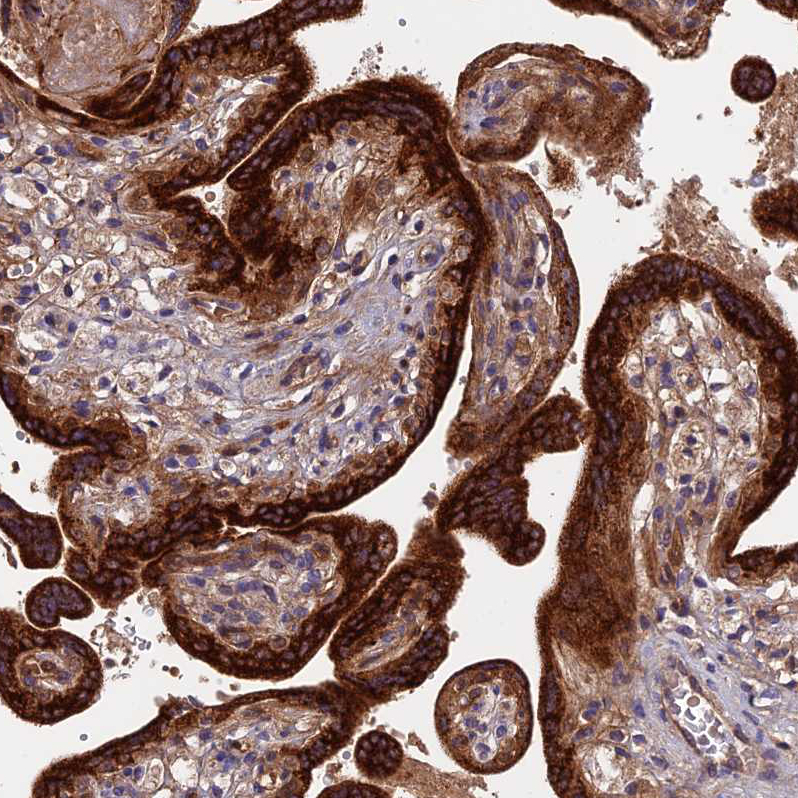

Immunohistochemical staining of human placenta shows strong cytoplasmic positivity in trophoblastic cells.